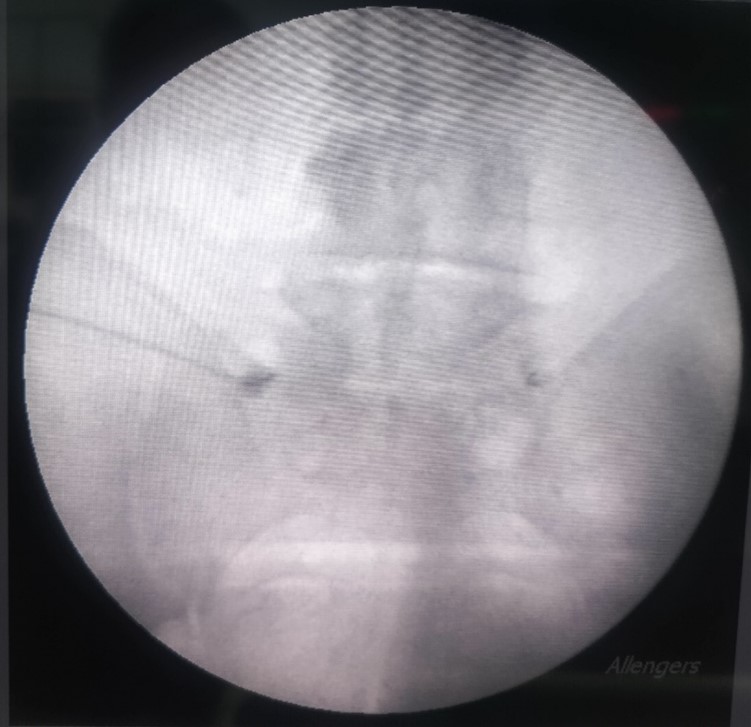

4. Medial branch rhizotomy/Radiofrequency ablation(RF):

- Patient selection: Predominant backpain in elderly patients that increases on twisting movements of spine is generally arising from facet joints. These patients have no leg pain.

- Technique: Facet joint pain is carried by medial branches of dorsal rami of spinal nerves or simply the medial branch. This technique damages this nerve, thereby treating the pain. A specialised instrument called radio frequency ablation is used that when set at desired frequency and amplitude produces heat to damage the medial branch.

- Expected result: Results last a minimum of 2.5-3 years after which procedure can be repeated. This technique is therefore better than facet injections.